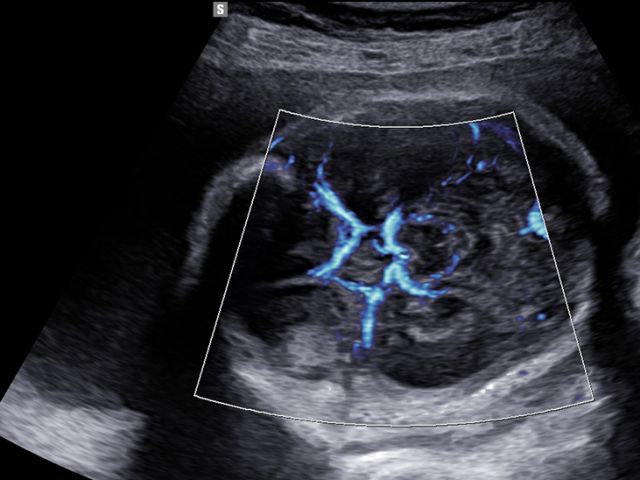

The color imaging performance has been improved to clearly visualize the hemodynamics of the blood flow. A greater sensitivity resulting from new color signal processing and a realistic 3D visualization of blood flow help understand the microcirculatory blood flows, accurate detection of peripheral blood vessels, and volumes of slow blood flows.

LumiFlow™ is a function that visualizes blood flow in three dimensional-like to help understand the structure of blood flow and small vessels intuitively.

MV-Flow™ visualizes microcirculatory and slow blood flow to display the intensity of blood flow in color. It is suitable for observation of microcirculatory blood flow and volume of slow blood flow.

The function uses directional power Doppler technology, enabling you to examine even the peripheral vessels. It displays information on the intensity and direction of blood flow.